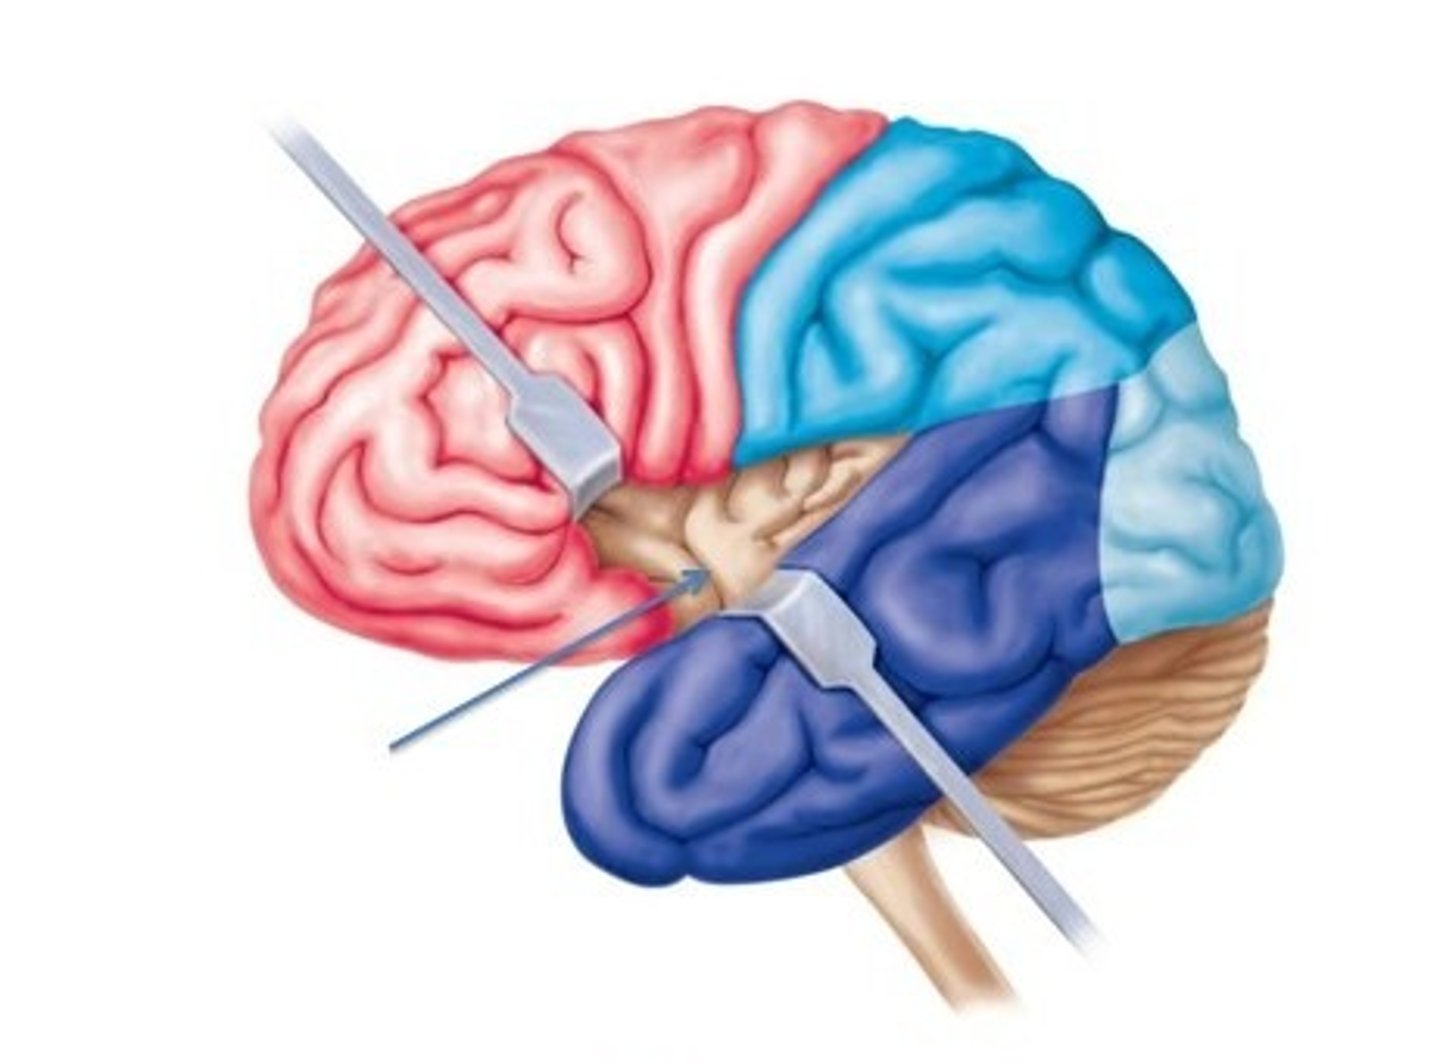

from central sulcus to front of brain. Motor speech area (Broca area), primary motor cortex, higher intellectual functions, personality, verbal communication, voluntary motor control of skeletal muscles.

parietal lobe

Information like taste, temperature, and touch are integrated here. Part of Wernicke area, primary somatosensory cortex, sensory interpretation of textures and shapes, understanding speech and formulating words to express thoughts and emotions.

occipital lobe

This is where the visual cortex is.

temporal lobe

This is where the primary auditory cortex is and the auditory association area. Primary auditory cortex, olfactory cortex, Part of Wernicke area.

insula

The fifth lobe of the brain in the lateral sulcus. Primary gustatory cortex.